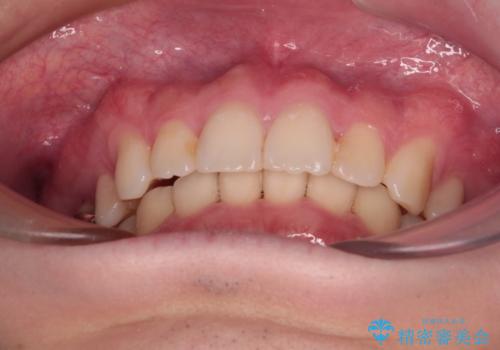

萌出が不十分な歯はインビザラインで引き出すことができないため、ワイヤー装置などの併用が必須となります。

今回は部分的にワイヤー矯正を用いましたが、右下の乳歯は全く動かなかったため、抜歯をした上でインプラントを埋入し、オールセラミッククラウンにて補綴治療を行いました。